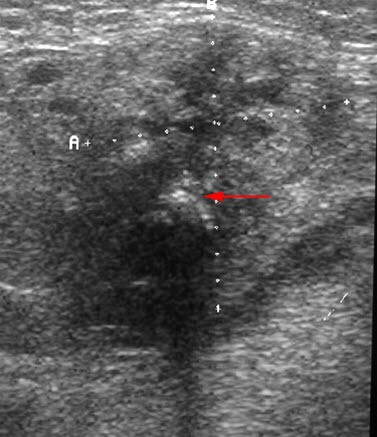

Kroniske betennelsesforandringer i glandula submandibularis med mikroabscesser og en forkalkning (pil) som gir ekkoskygge